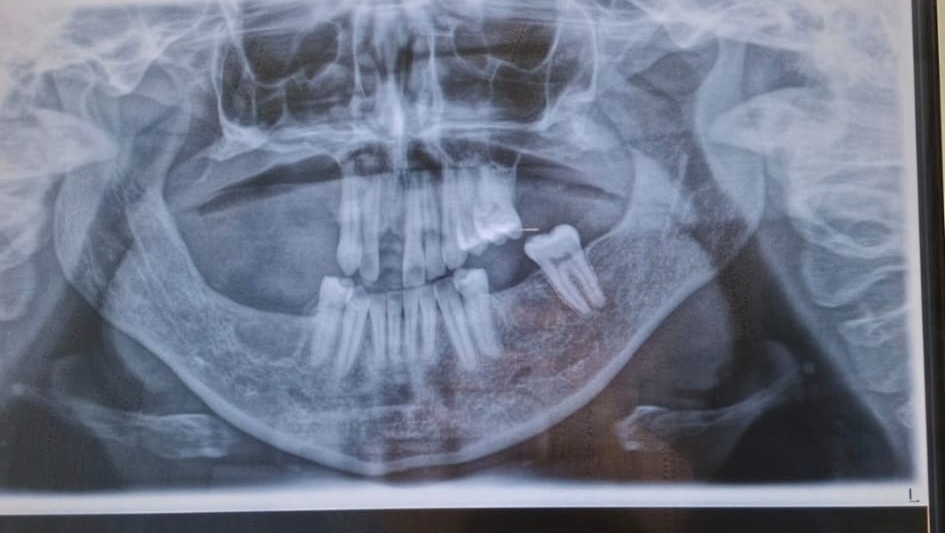

Leider gibt es keine langfristigen Studien zu dem Medikament, doch es existieren Berichte, dass es Entzündungen im Kieferknochen und Zahnapparat verursachen kann. Diese Entzündungen sind auf Röntgenbildern schwer bis überhaupt nicht erkennbar. Meist nur im CT oder in einem DVT. In meinem Fall sprechen die Ärzte von einer diffusen -und chronischen Osteomyelitis. Das heißt, es sind bereits zwei Formen der Osteomyelitis in meinem Kieferknochen zu finden.

Back to my jaw – aside from the movement issues, I have no molars left. The last one will be removed in February 2026. Since the last supporting bones of the jaw are still standing, it's hardly noticeable. Except for the fact that my cheeks are sunken because there's hardly any bone left there. The area under my nose is also still inflamed and will eventually need to be removed.

Without jawbone and teeth, you can no longer speak properly. Aesthetically, you're ruined, as the extent of the damage is comparable to that of a tumor removal. Unfortunately, as I mentioned, the lower jaw is also affected.

Unfortunately, a lot of bone has already been removed. The bone marrow is inflamed and causes extreme pain. Although my teeth are well-maintained and healthy, the inflammation is spreading to the tooth roots.

At the same time, the bone marrow inflammation is destroying the bone. The bone becomes mushy and soft, causing teeth to loosen and fall out with excruciating pain, or eventually requiring extraction.

So far, the only relief I've found is the removal of the affected jaw sections, along with strengthening my immune system. However, there's a limit to the amount of bone that can be removed from the face, which is why everything possible must be done to stop the inflammation.

Extensive partial removals have already been performed. This missing bone cannot be restored with implants, crowns, or any other procedures, as nothing of the sort can be built on inflamed bone. Unfortunately, it's also suspected that the bones in other parts of my body aren't healthy. Therefore, a bone transplant from my leg, shoulder, or pelvis isn't an option. They assume it will be a lifelong process for me, until I completely lose my upper and lower jaw.

Unfortunately, there are no long-term studies on the medication, but there are reports that it can cause inflammation in the jawbone and teeth. This inflammation is difficult or impossible to detect on X-rays, usually only visible on CT or CBCT scans. In my case, the doctors are talking about diffuse and chronic osteomyelitis. This means that two forms of osteomyelitis are already present in my jawbone.

Weakening of the jawbone and its joints due to years of cortisone medication. Additionally, a pre-diabetic condition developed as a permanent side effect (insulin resistance). Hormonal imbalance (+PCOS) and impaired metabolic processes (persistent weight gain of 25 kg + triggering of lipedema). This is also due to the lipedema in the arms and legs. However, another suspected trigger for the condition could be a medication (name withheld) that suppresses the immune system. According to several oral and maxillofacial surgeons, the side effects of this medication are similar to those of chemotherapy. Unfortunately, there are no studies to support this. The long-term effects are still unknown. Furthermore, blood flow in the jawbone is compromised due to a major orthodontic surgery performed in the past. Inflammatory processes begin at these former fracture and fixation sites of the plates/screws. Bacterial involvement has only been partially, and in some areas not at all, confirmed. Unfortunately, bacteria can form a biofilm and become encapsulated. Certain antibiotics are sometimes helpful, at least for a limited time.

Furthermore, a bone metabolism disorder is suspected. However, the standard tests for this were negative. Clinical wound healing on the bone itself, however, suggests something else. Overall, there is poor blood circulation and bone damage due to several known, but also unknown, factors.